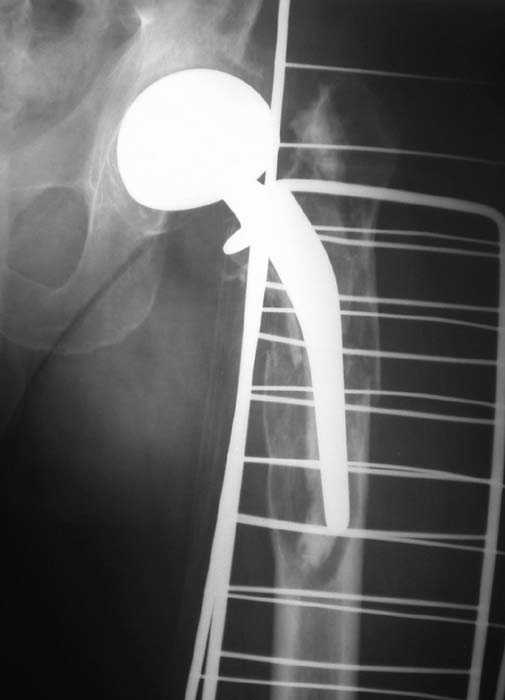

Мужчина, 39 лет.По поводу двустороннего асептического некроза головок бедренных костей последовательно выполнено тотальное эндопроезирование левого (1998 г), затем правого (1999 г) тазобедренных суставов.

11/07/04

С 2001 г отмечает нарастающие боли в левом бедре. Предполагается удаление протеза, удаление цемена из канала бедра, пластика дефекта бедренной кости.

Нет никакого смысла делать операцию в два этапа. С чашкой все понятно - стандартный подход с установкой пресс-фит компонента. На бедре имеет

место перипротезный перелом В3 типа - т.е. перелом вокруг ножки с ее нестабильностью на фоне выраженного остеолиза. Решение - доступ к каналу

через перелом с удалением самой ножки, костного цемента и рубцовых тканей. Установка ножки дистальной фиксации (типа Solution), длину ножки

надо определить по шаблону. Минимальный контакт ножки с интактной костью - 6-8 см. Фрагменты проксмального отдела собираются на ножке

эндопротеза, дефекты костной ткани заполняются чипсами (аллографт) и фиксируются кортикальными аллографтами, уложенными дополнительно по типу

"вязанки хвороста" серкляжом. Мы имеем 8 или 10 подобных наблюдений и результатами довольны.